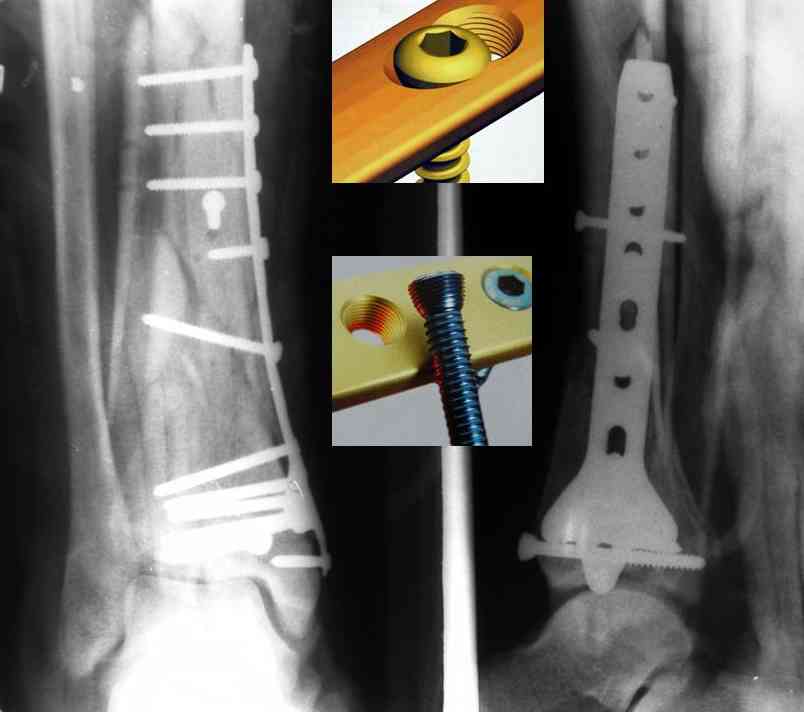

Кстати, при переломах переднего края по классификации АО В-3 при переломах пилона пластина укладывается по передней поверхности. Она достаточно тонкая и эластичная, не надо этого бояться. Посылаю три снимка.

Ja operiroval bolnogo po Vashemu, hotia sam ni ochen' ubezden' v itom, t.k. bolnoi otkazalsa na proch' ot ex.fix, ja emu sdelal ORIF + Kostnia plastika, snimky prelogiottsa,

Isskrenny Vash Castro